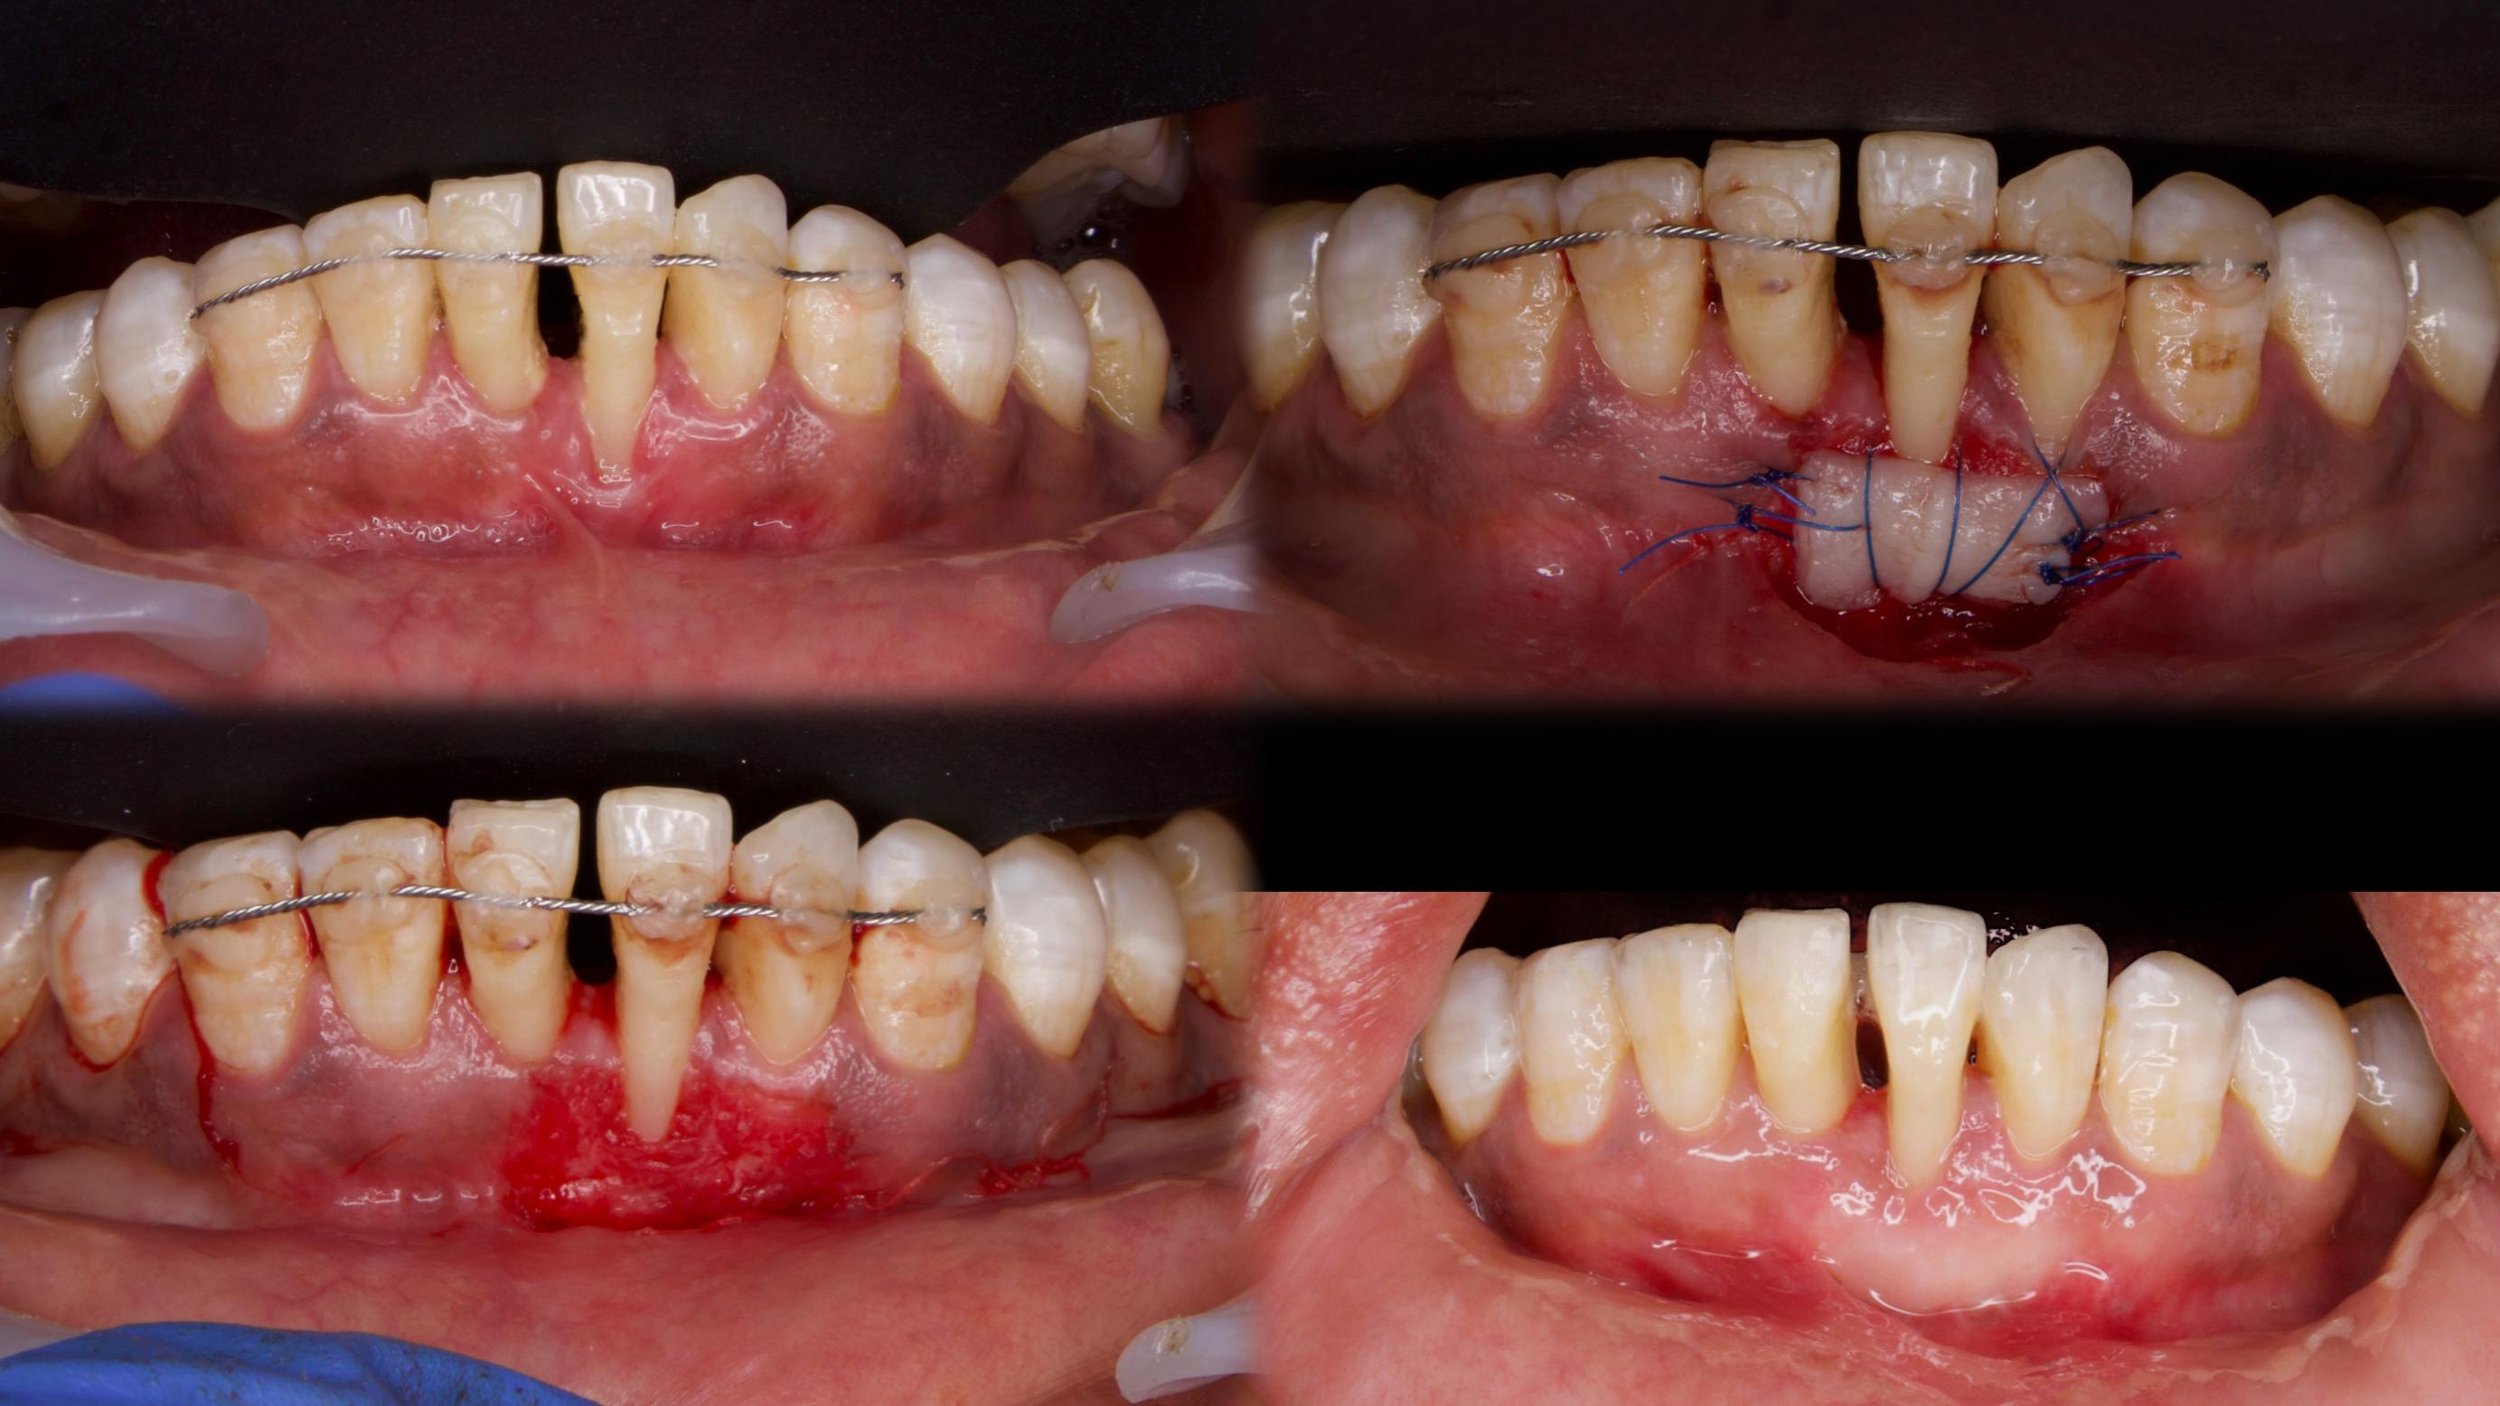

PAPILLA RECONSTRUCTION SURGERY WITH CONNECTIVE TISSUE GRAFT (Lower anteriors)

Surgery performed by Dr Mohammed Thaha

Periodontics SaveethaNovember 26, 2024